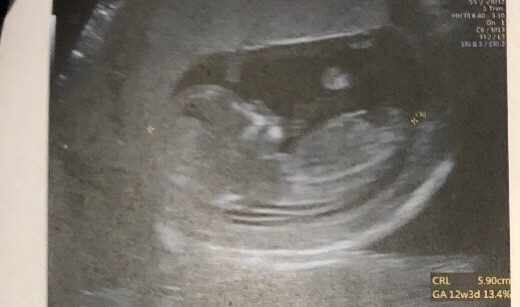

Cześć dziewczyny proszę was o ocenę zdjęcia usg... Miesiąc temu zapowiedzieli mi syna a 4 grudnia na połówkowym ze córka... Trochę mam mętlik w głowie 😞

Niestety tylko wydruk z badań prenatalnych w różnych rzutach, tak żeby było widać nub jest jedno (tez średnia jakość :/) ale widać.